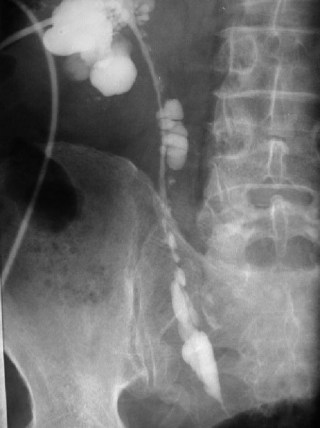

Signo de rotura vesical extraperitoneal en la cistografía. La extravasación del contraste hacia los tejidos blandos extraperitoneales y, especialmente hacia el espacio prevesical de Retzius, da un aspecto característico de «llamaradas» o «resplandor solar“ (flechas verdes).

Obsérvese la fractura de rama ilio-pubiana derecha (flecha azul) y la diástasis de la articulación sacroilíaca izquierda (flecha amarilla).